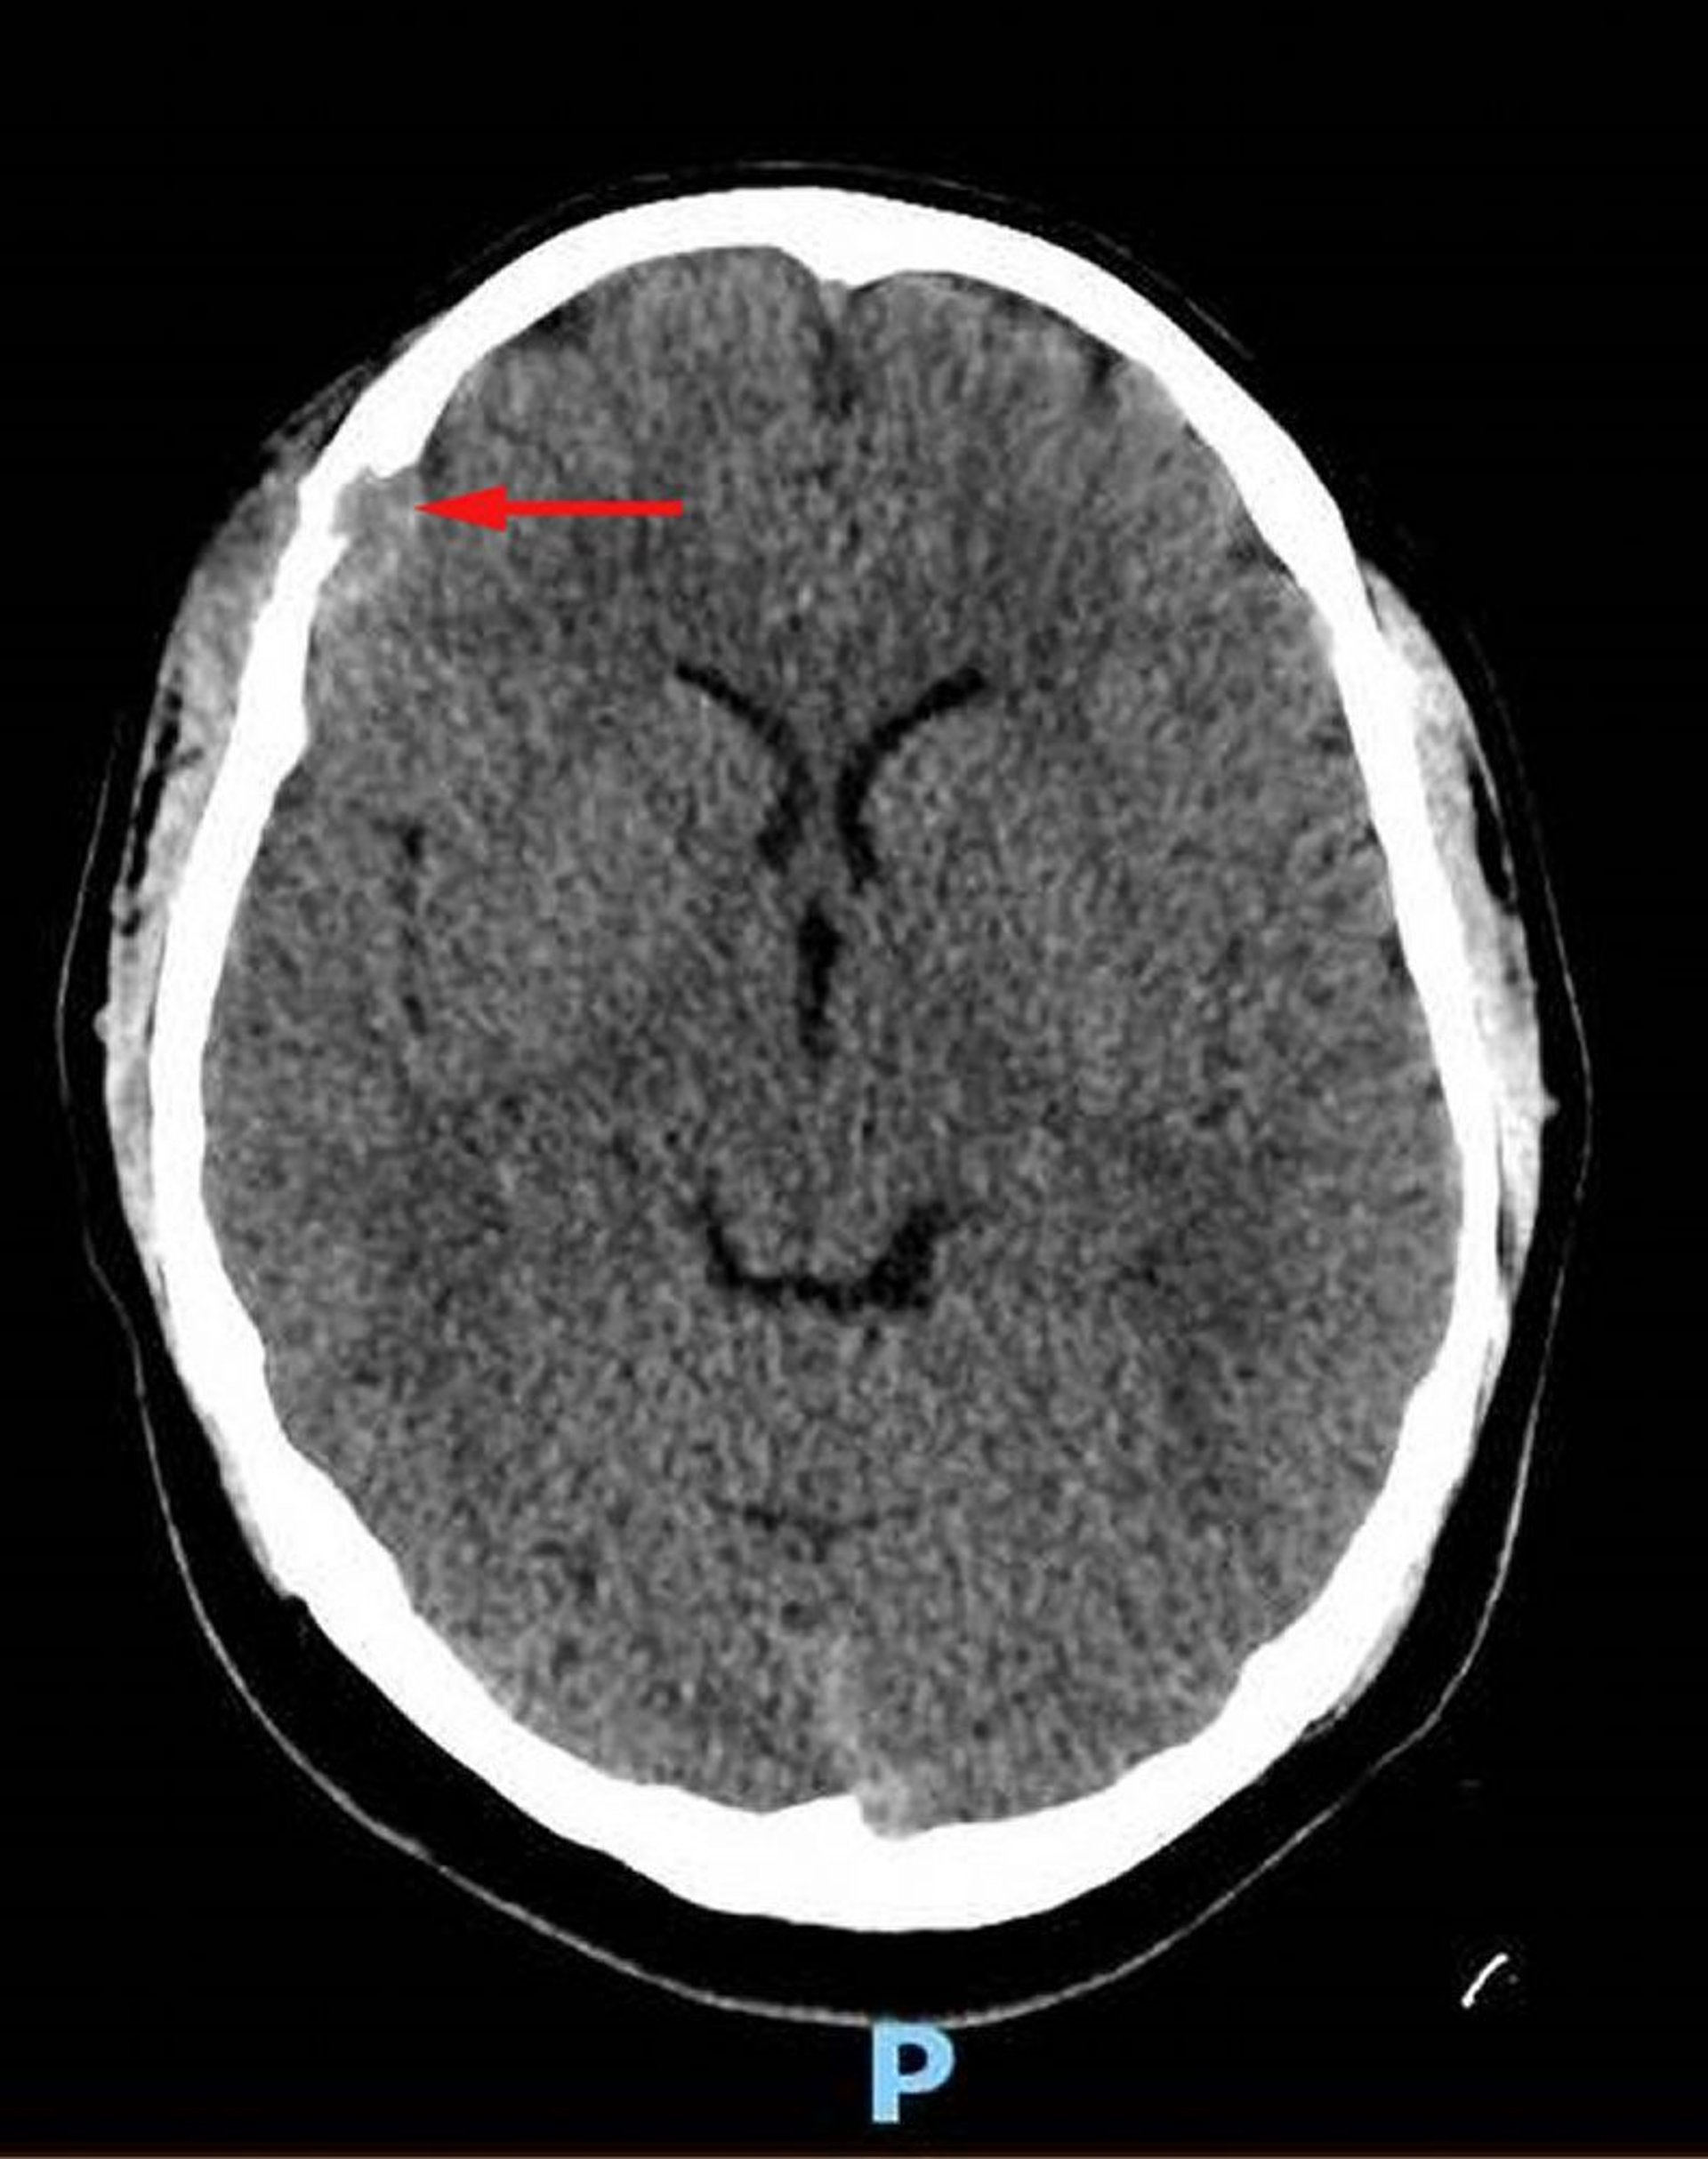

Histiocitosis de células de Langerhans (TC craneal)

Esta imagen muestra una lesión del tejido blando en el hueso frontal derecho con destrucción ósea asociada y extensión intracraneal de tejido blando en el espacio dural (flecha roja). Se observa tejido blando asimétrico sobre el cuero cabelludo. La biopsia fue diagnóstica para histiocitosis de células de Langerhans.

Image courtesy of Carolyn Fein Levy, MD, and Jeffrey M. Lipton, MD, PhD.